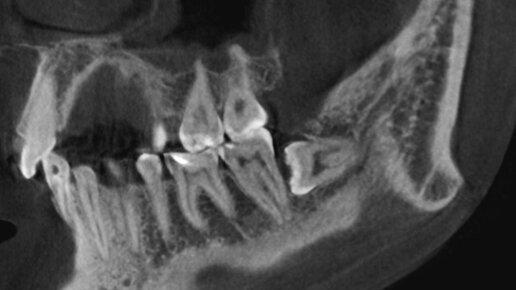

Но всё ли так просто? Надо ли удалять их всем подряд? Или, наоборот, стоит бороться за каждый «родной» зуб до последнего? Разбираемся, когда зубы мудрости действительно стоит удалить, а также какие последствия ждут, если игнорировать проблему. Это третьи моляры, которые прорезаются последними — обычно в возрасте от 17 до 25 лет. Но часто бывает так, что: Если зуб не выходит полностью, он может «застрять» в кости и вызывать хроническое воспаление — ретенцию...